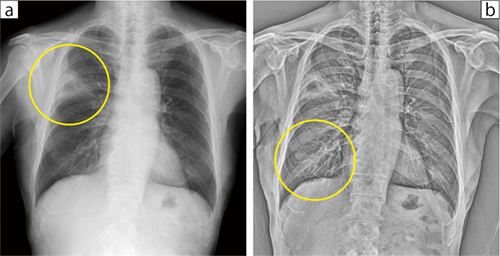

症例1は,X線動態画像で右上中肺野に位置する浸潤影を伴った腫瘤影(図1 a○)が肋骨陰影から動く様子がなく,癒着していると判断して開胸手術を選択した。なお,FE-MODEでは,中下肺野末梢の肺血管は肋骨とずれて動く様子が確認できたため(図1 b○),その部位での癒着が少ない,もしくは癒着がないと考えられた。手術所見では,腫瘍部分は広範に癒着が認められ,中葉・下葉部分の癒着はごく一部だった。

図1 症例1:癒着あり症例